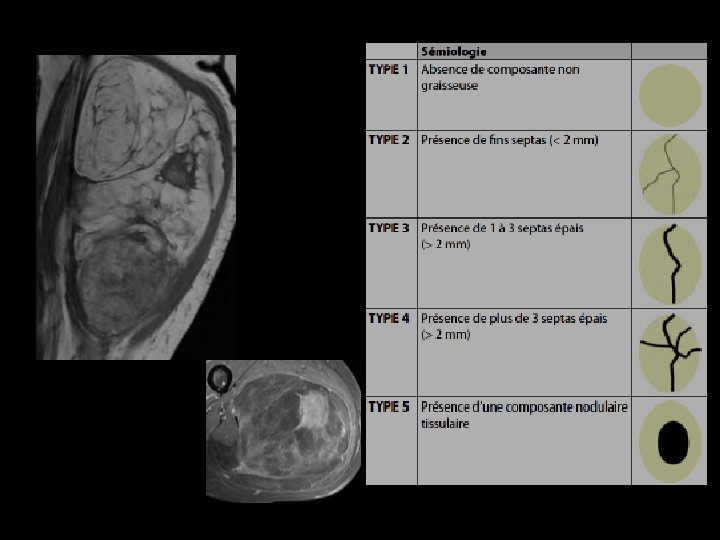

LIPOSARCOME BIEN DIFFERENCIE IRM: • Masse de signal graisseux - en hypersignal T 1 et T 2 - effacement du signal de la graisse • En faveur de la malignité: - septas épais > 2 mm - éléments nodulaires et tissulaires

Liposarcome bien différencié de l’épaule. IRM en coupe axiales en séquences pondérées T 1 (a) et T 1 fat-sat gado (b). Septa épais se rehaussant après injection de Gadolinium contrairement au reste de la tumeur graisseuse

Liposarcome bien différencié de la loge postérieure de la cuisse IRM en coupe axiale (a) et sagittale (b) en séquences pondérées T 1. Volumineuse tumeur de signal graisseux présentant des septa épais et des nodules tissulaires intratumoraux (têtes de flèches).

a Liposarcome bien différencié de la loge postérieure de la cuisse. IRM en coupe axiales en séquences pondérées T 1 (a) et T 1 fat-sat gadolinium (b) La présence d’un volumineux nodule tissulaire intra tumoral se rehaussant de façon important (flèches) est très en faveur de la malignité de la masse. b

Liposarcome bien différencié de la hanche Coupe axiale pondérée SE T 1 (a), frontale pondérée T 2 (b) et axiale pondérée SE T 1 avec Fat Sat et injection de Gadolinium (c): tumeur graisseuse avec des travées nombreuses et relativement épaisses

TUMEURS GRAISSEUSES BENIGNES LIPOME Localisation superficielle Taille < 5 cm Homogène Sépta < 2 mm Pas de nodules MALIGNES LIPOSARCOME BIEN DIFFERENCIE Localisation sous aponévrotique Taille >5 cm Hétérogène Sépta épais Éléments nodulaires et tissulaires